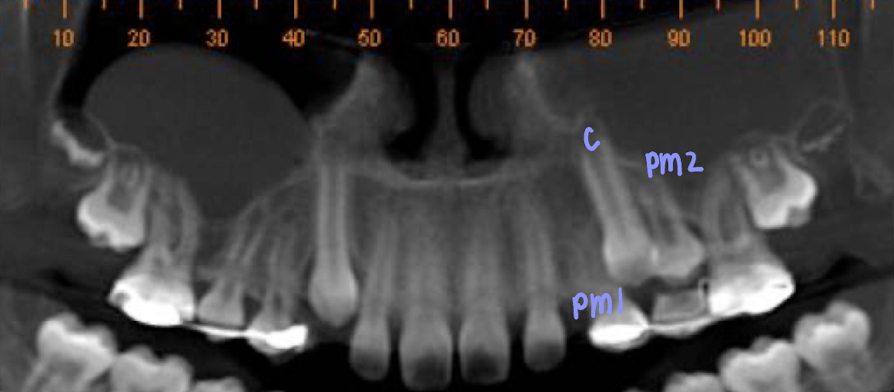

What dental anomaly does this patient have?

Transposition